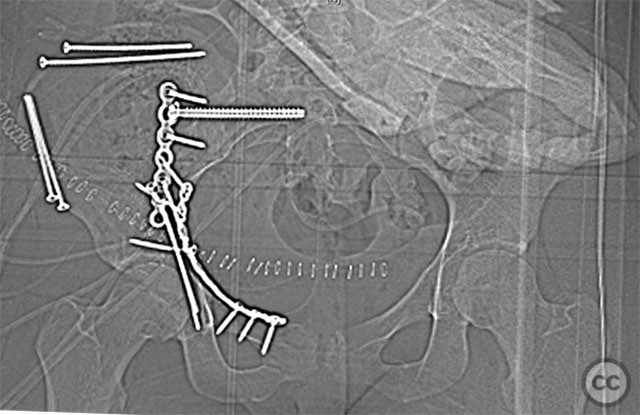

Clinical and radiological findings:  A 19-year-old female sustained a high-energy injury in a motor vehicle accident. Initial AP pelvic radiograph demonstrated a right-sided, displaced, comminuted associated both column acetabular fracture (AO/OTA 62C3), with a separate fracture fragment involving the greater sciatic notch (GSN). The right sacroiliac (SI) joint was incompletely disrupted. Surface rendered CT images confirmed the complex fracture morphology, including the separate GSN fragment and the SI-sacral injury, which rendered the typical posterior iliac fragment non-intact. Axial CT at the acetabular dome level revealed multiple displaced fragments and provided further detail regarding soft tissue involvement.

The SI joint injury was addressed first, with reduction under direct visualization and percutaneous screw fixation across the SI joint. The anterior column fragment was then reduced anatomically. The separate GSN fragment was identified and reduced using clamps via the intrapelvic window; a lag screw was placed through the initial reconstruction plate to secure this fragment. The posterior column was subsequently reduced and stabilized with additional fixation as indicated by intraoperative assessment. The presence of a separate GSN fragment and ipsilateral SI injury necessitated careful sequencing of reduction and stable fixation to restore pelvic ring integrity.

Orthopaedic implants used:   Pelvic reconstruction plate(s), cannulated SI screw(s), lag screw(s)